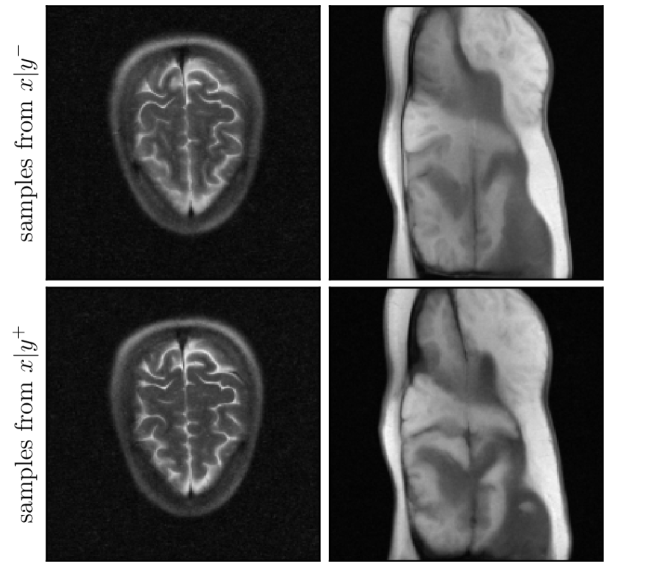

We now consider a single-coil MRI image reconstruction problem (see SM, Section 9). We use two diffusion priors from [shoushtari2025unsupervised], which are trained on brain and knee images from the FastMRI dataset respectively [zbontar2018fastmri, knoll2020fastmri]. We consider the brain dataset as ID. We proceed similarly to the previous experiment and extract brain and knee scans from FastMRI to compose the ID and OOD datasets. For this experiment, we slightly increase α\alpha to 0.250.25 to reduce the noise injected to 𝐲\mathbf{y}^{-}, which allows reducing the number of noise realizations to 44 and the number of steps to 1010. We define a reference dataset of 5050 brain scans to compute the 9595-th percentile of Φ^y2\widehat{\Phi}^{2}_{y}, and compose a test set of 5050 ID and 5050 OOD images. We set the measurement noise to 0.10.1 in all experiments and consider an acceleration factor RR of ×4\times 4 or ×8\times 8 for the forward operator; increasing RR makes the estimation problem more challenging.

The values of the estimators Φ^y1\widehat{\Phi}^{1}_{y} and Φ^y2\widehat{\Phi}^{2}_{y} and for the brain-trained model are represented in Fig. 9 for R=4R=4 and the more challenging case R=8R=8. In both cases, we observe an excellent discrimination between ID and OOD data points for both estimators. This result can be explained by the fact that the brain images comprise few learnable features that can be transposed to knee images. The brain model mainly learns the complex structures (gyri) present on the surface of the brain, which are completely absent from knee scans, and it tends to hallucinate these structures in knee reconstructions.

Figure 10: Samples from x|yx|y^{-} and x|y+x|y^{+} for the brain-trained diffusion model on ID and OOD examples.

Moreover, to evaluate OOD detection accuracy, Tab. 3 reports the Type I error probability and testing power obtained with each estimator; we observe that they both achieve excellent performance. For completeness, we also report the results for single-shot model selection against a model trained on knee scans in SM, Section 9. Lastly, Fig. 10 shows examples of samples from p(x|y)p(x|y^{-}) and p(x|y+)p(x|y^{+}) for ID and OOD cases. Once again, we observe that the OOD case exhibits substantial variability in perceptual details, largely hallucinated by the prior.